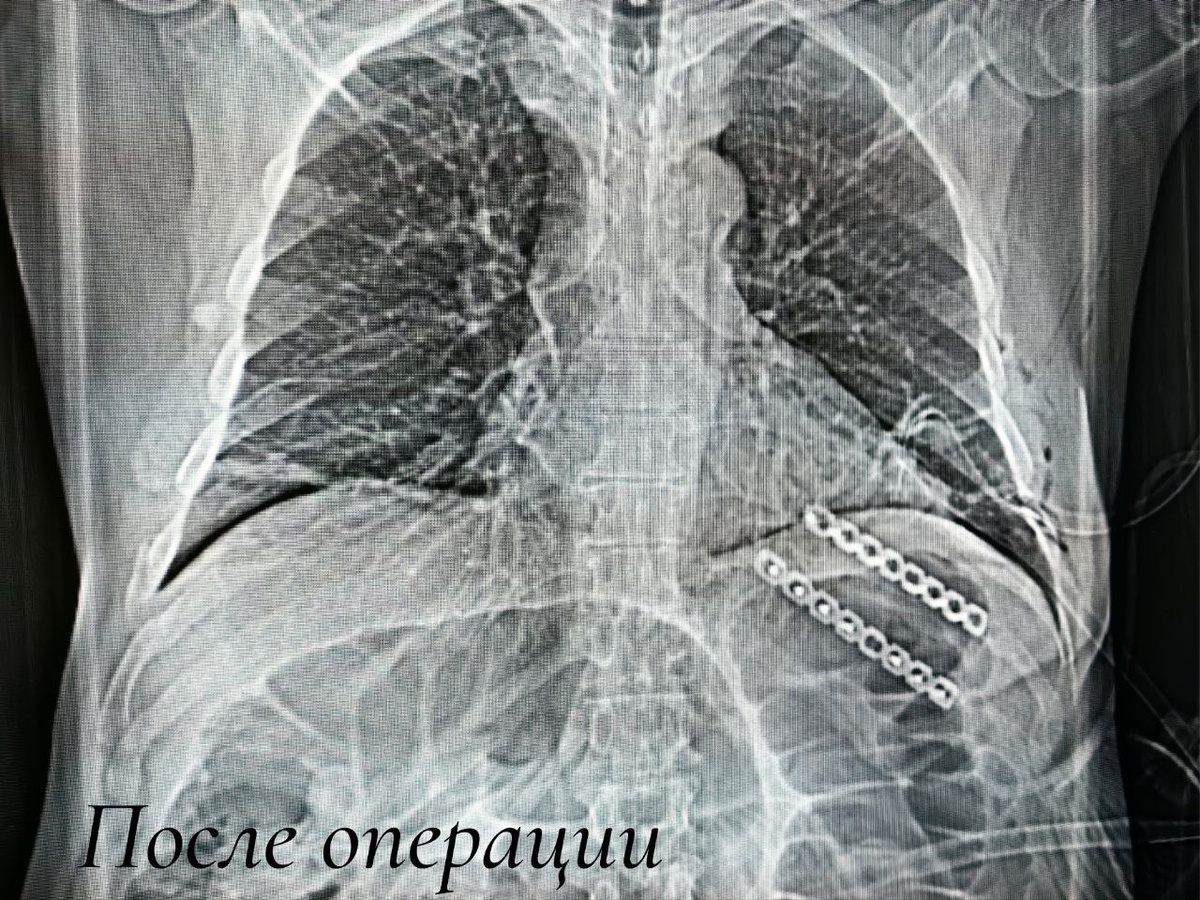

59-летний житель Советского поступил с редким последствием производственной травмы - посттравматической грыжей лёгкого. Дело в том, что после множественного перелома ребер два из них не срослись из-за разрыва межрёберных мышц. В результате лёгочная ткань переместилась за пределы грудной клетки. Подобные операции в нашем регионе выполняют только в травмцентре. Через минимальные проколы хирурги вернули лёгкое в плевральную полость и устранили грыжевой дефект. Через открытый доступ восстановили анатомию рёбер, зафиксировав их специальными пластинами. Конструкцию удалять не потребуется. Вмешательство выполнили Дмитрий Горлов, Сергей Глиняный и Евгений Николаев. Сложную технику однолегочной вентиляции обеспечил анестезиолог-реаниматолог Виталий Реннер.

Подобные операции в нашем регионе выполняют только в травмцентре. Через минимальные проколы хирурги вернули лёгкое в плевральную полость и устранили грыжевой дефект. Через открытый доступ восстановили анатомию рёбер, зафиксировав их специальными пластинами. Конструкцию удалять не потребуется.